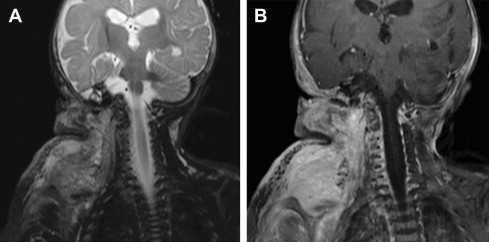

Kaposiform hemangioendothelioma (KHE) is a rare vascular neoplasm with locally aggressive characteristics but without metastatic potential. MRI typically shows an ill-defined soft tissue mass that is hypo- or isointense on T1-weighted imaging and hyperintense on T2-weighted imaging. On administration of contrast, there is intense but heterogeneous enhancement ( Fig. 5 ). Subcutaneous fat stranding is an important feature that helps differentiate KHE from other benign fast-flow vascular masses. Prominent vascular channels, evidenced by flow voids, are usually present on MRI studies.